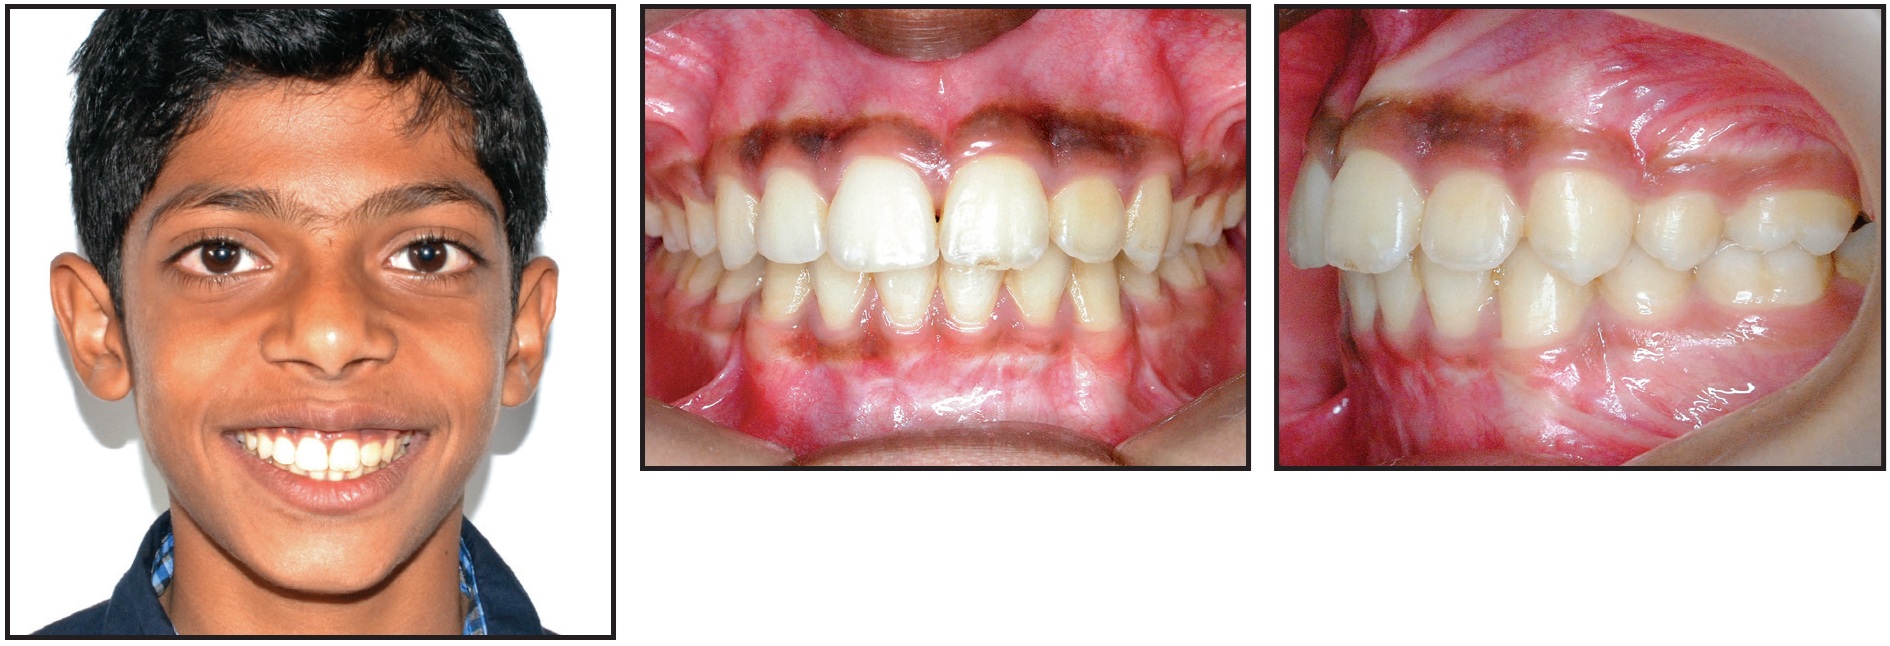

Ideal overbite and overjet relationships were established, with proper intercuspation and coincident upper and lower midlines (Fig. 4A). The final occlusion demonstrated proper interproximal contacts and root parallelism. Periodontal evaluation showed an acceptable gingival contour and adequate width of keratinized attached gingival tissue around the disimpacted teeth.

Superimposition of cephalometric tracings confirmed a consistent skeletal relationship and improved overjet and overbite, due to both treatment effects and favorable growth (Fig. 4B, Table 1).

Fig. 4 A. Patient after 30 months of active treatment. B. Superimposition of pre- and post-treatment cephalometric tracings.

One year after orthodontic treatment, the occlusion and smile remained stable (Fig. 5).

Fig. 5 Patient one year after debonding.